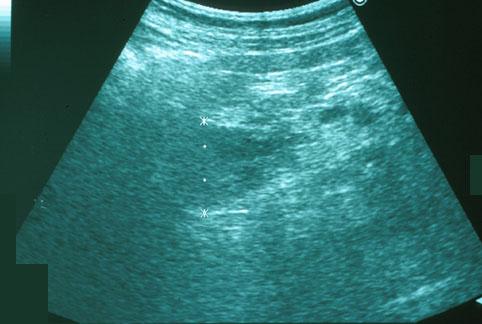

症例提示(所在地,施設名等): 長崎県・ 長崎医療センター

疾患(病理主体)の分類悪性上皮性腫瘍/腺癌

部位(臓器別)十二指腸/乳頭部

検査方法エコー

病変の最大径(ミリ)20〜24